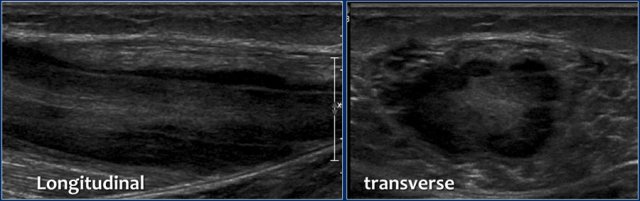

Here another patient.

Notice the longitudinal orientation of the lesion along the muscle fibers on the longitudinal image.

On the MR the lesions are almost identical compared to the other patient.

Notice the orientation on these coronal images.

There is some edema, but almost no mass effect.

On these axial T2W-images with fatsat notice again the strange appearance of these lesions.